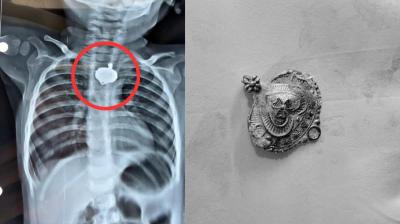

बड़वानी में 9 माह के बच्चे की आहार नली में फंसा मंगलसूत्र, डेढ़ महीने बाद एक्स-रे से खुलासा

24 Nov, 2025 08:30 AM IST | MP18NEWS.COM

बड़वानी: रविवार को जिला अस्पताल में एक बेहद संवेदनशील और हैरान करने वाला मामला सामने आया. जब 9 माह के एक बच्चे के गले में मंगलसूत्र फंसा हुआ देखा गया. घटना...